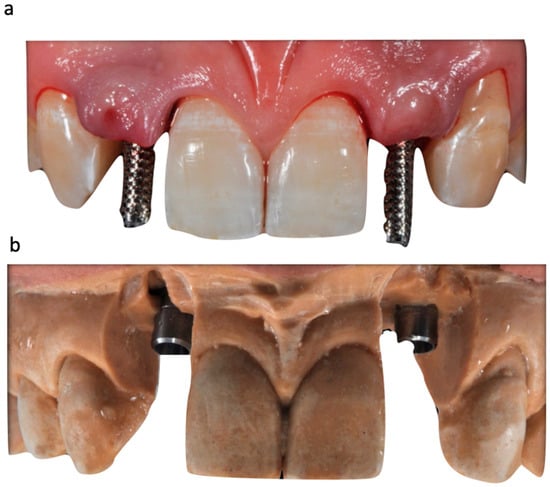

The case describes rehabilitating two congenitally missing lateral incisors in a young patient (38 years old) undergoing orthodontic treatment to create the necessary space for implant placement (Figure 1 and Figure 2). Two fibre-reinforced composite Maryland bridges (Tender Fiber Quattro—Micerium) were utilised for provisional rehabilitation (Figure 3, Figure 4 and Figure 5). Two Osstem TSIII 3.5 × 10.0 implants (1.5 mm subcrestal), two straight Osstem Zirconia abutments, and two-layered lithium disilicate crowns were employed for the definitive restoration (Figure 5, Figure 6, Figure 7, Figure 8, Figure 9, Figure 10, Figure 11, Figure 12, Figure 13, Figure 14, Figure 15, Figure 16, Figure 17, Figure 18, Figure 19 and Figure 20) [,]. The dental implant position was planned after a three-dimensional radiographic analysis in a prosthetically guided way. Patient rehabilitation was performed with an immediate post-surgery provisional (Maryland-type, cemented with a resinous cement) application. Subsequently, a delayed loading of the new provisional dental implant was retained (cemented with zinc oxide eugenol cement) and finally, definitive crowns (cemented with a definitive resinous cement) on Osstem® abutments were installed (3 months).

Figure 10. (a,b) Uncovering and delivering provisional restorations on implants with radiographical exam details. (c) Provisionals are delivered directly during uncovering for guided soft tissue healing.

Figure 16. Gingival profiles (a,b) and inserted abutments (c,d).

Figure 17. Mucosal profile (a) and crown placement (b,c) (fabricated with lithium disilicate ceramics (e-max)).

The position of the dental implants was recorded during the surgical insertion using a transfer key fabricated based on the initial model (before surgery). Subsequently, our technician duplicated the wax-up and soft tissues with precision systems and transferred the implant positions to the working model, providing us with a provisional restoration that had already been inserted during implant uncovering (Figure 6, Figure 7, Figure 8 and Figure 9). We transferred the definitive emergence profile, conditioned by the provisional without periodontal surgery techniques, to the laboratory by recasting the artificial gum on the model (Figure 11, Figure 12 and Figure 13) through the finalized provisionals (Figure 14). At this point, the laboratory had all the information required to construct an individualised and treated abutment, using appropriate processing techniques to achieve a natural-looking response together with the metal-free prosthetic crown.

Initial models and diagnostic wax-ups were created using silicone (Elite HD+, Zhermack) with a closed tray technique, and provisional restorations were fabricated using different colours of acrylic resin (Jet Kit®, Lang, IL, USA). Temporary restorations were then placed in position (Figure 5). A transparent resin transfer key was employed to streamline the implant’s placement. The information regarding the implant’s position was conveyed to the laboratory through a series of specialized steps. These included the installation of titanium temporary abutments sourced from Osstem® in South Korea, securing the workpiece within the transfer key using pattern resin, precision drilling on the master hard stone model (Figure 6, Figure 7 and Figure 8), and an accurate placement of analogues in this model by employing a recasting technique with hard stone material (Figure 9). After revealing the implanted components, provisional restorations were promptly delivered as part of the uncovering procedure to encourage optimal soft tissue healing (Figure 10). Adjustments were made to the emergence profile to condition the surrounding soft tissues properly, and specialized conditioning procedures were carried out (Figure 11 and 12). Before and after conditioning, the changes in the profiles were documented (Figure 13). The new profiles obtained were transferred to the master model by mounting the modified provisional restorations with analogues, and a new artificial gum was created through recasting (Figure 14). Once the soft tissues had healed correctly, guided by the modified and polished provisional as in Figure 11, it was possible to transfer the mucosal profile onto the master model. By removing the provisionals from the oral cavity, they were then positioned on the master model, corresponding to the dental implant analogues in the master model. The master model that had previously been modified and freed from any over contours or undercuts was relined at this point with a laboratory silicone to simulate the profile of the mucosa. The abutments were customised using ceramic and fluorescence techniques to achieve optimal emergence profiles (Figure 15). Gingival profiles were assessed, and the abutments were inserted accordingly (Figure 16 and Figure 17). The final stage involved the placement of crowns, which were fabricated using ceramic material (E.max ceram®, Ivoclar, Naturno, Italy). A last radiographic check was performed to ensure a proper alignment and fit of the restorations. The case was considered completed, and aesthetic integration was achieved. Overall, this case report encompassed various steps, including an initial assessment, diagnostic procedures, provisional restorations, implant placement, emergence profile modifications, abutment customisation, crown placement, and the final evaluation of the completed case.